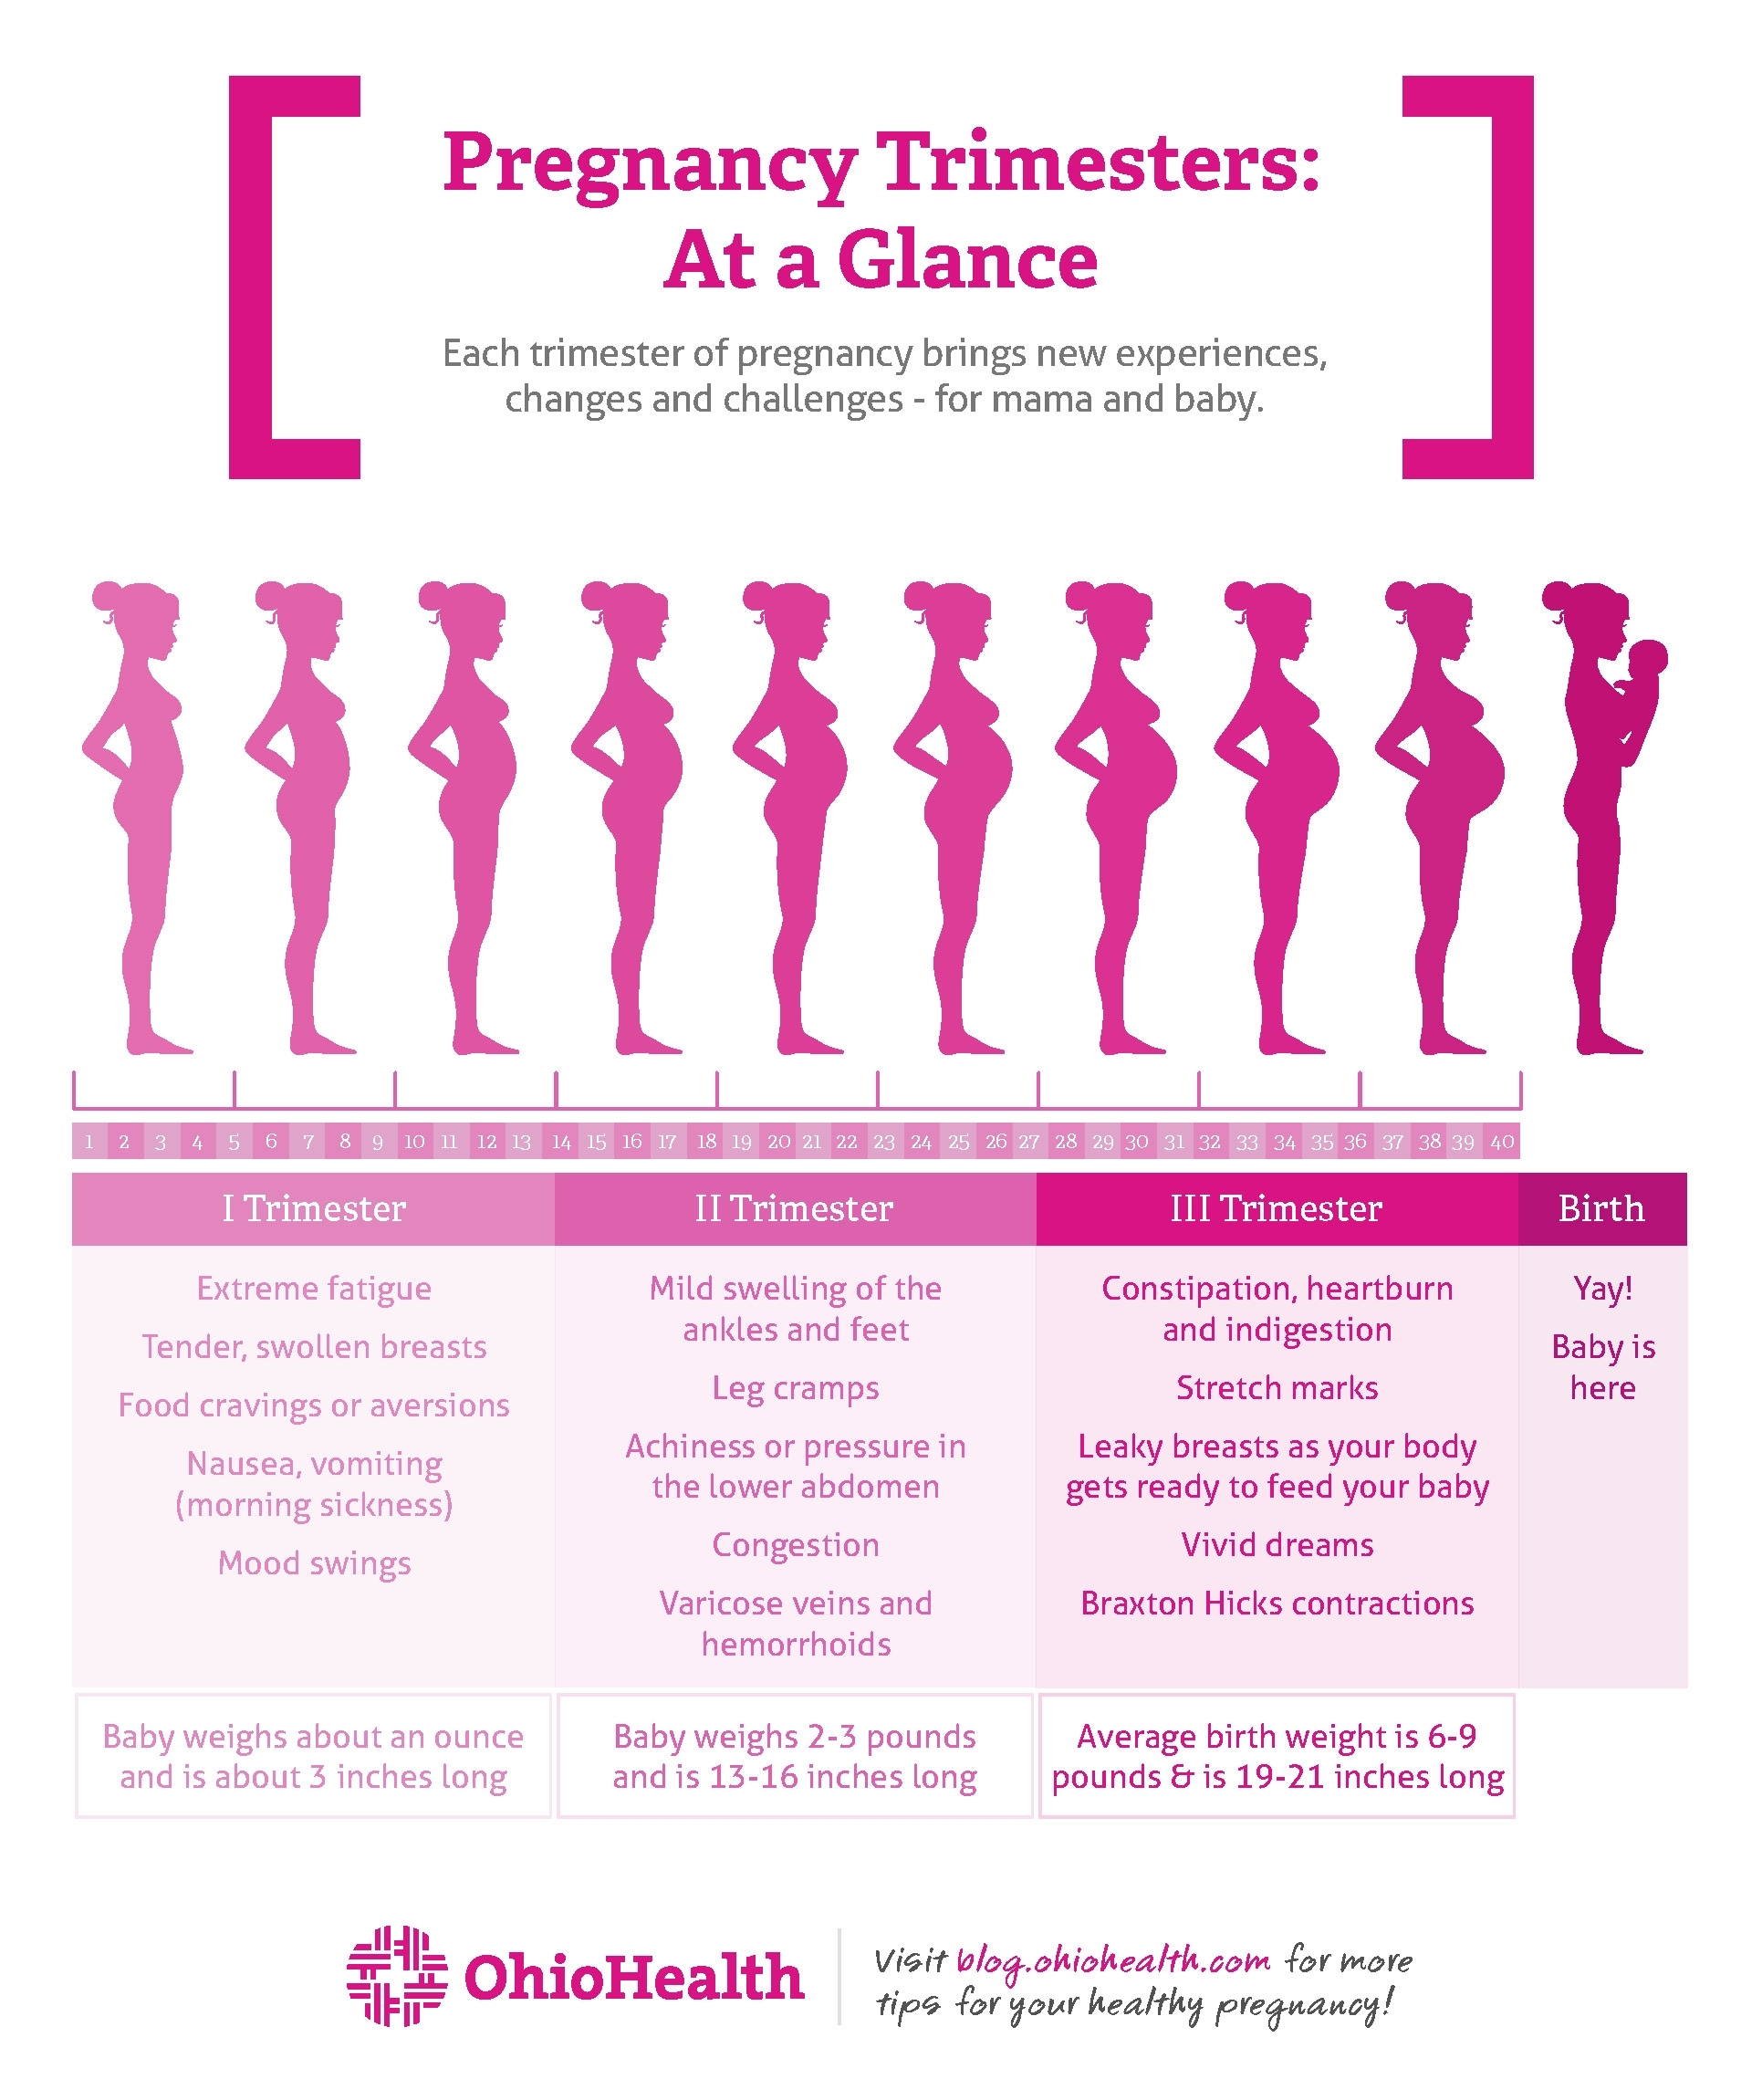

The Best How Many Weeks Pregnant Is Considered Full Term Ideas …

Pregnancy Stages Months And Weeks

Full Term Pregnancy 36 Weeks / Quick Answer Is Baby Fully Developed At …

Pregnancy Stages! How Many Weeks Are You Pregnant? – New Moms Forum

How Many Weeks Are In A Full Pregnancy – PregnancyWalls